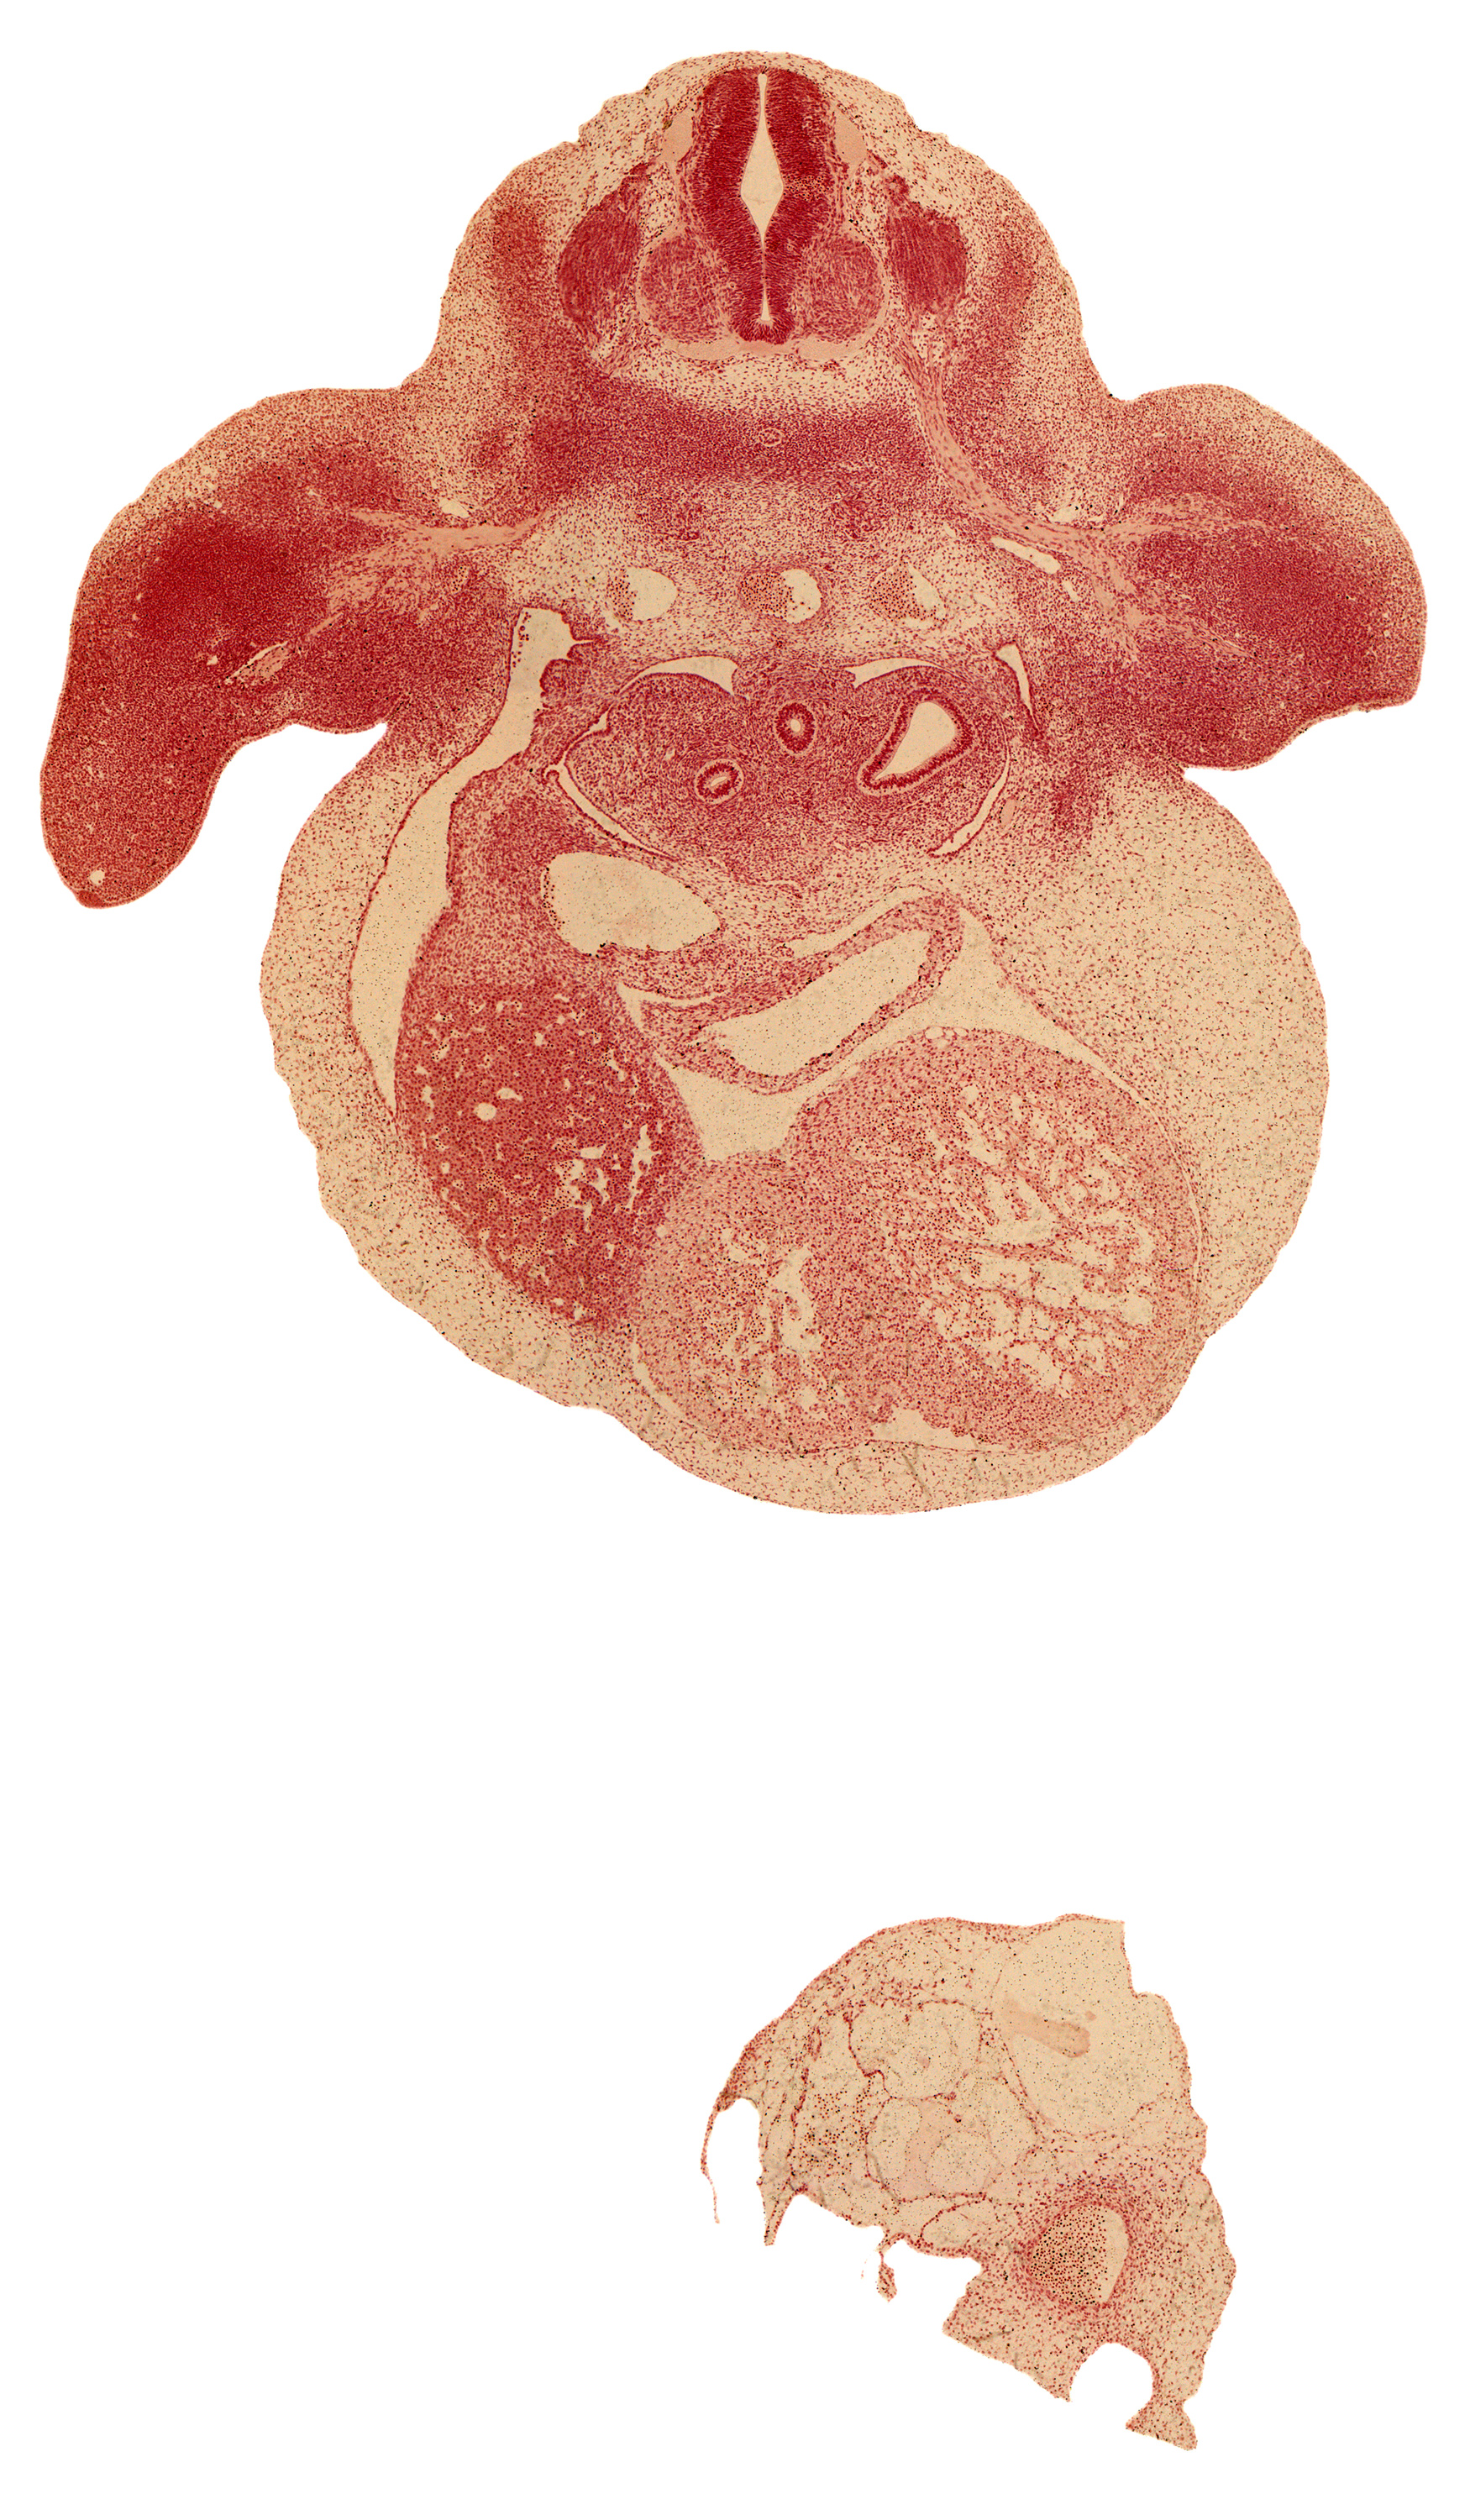

Carnegie Embryo #6517   |   Location: 24-02-01

Keywords: C-7 spinal ganglion, C-7 ventral primary ramus, alar plate(s), aorta, basal plate, brachial artery, cardiac prominence, dorsal meso-esophagus, edge of peritoneal cavity, esophagus, left horn of sinus venosus, liver, marginal vein, pericardial cavity, primary bronchus, septum transversum, sinus venosus, skeletal blastema of humerus, sulcus limitans, upper secondary bronchus bud

Source: The Virtual Human Embryo.